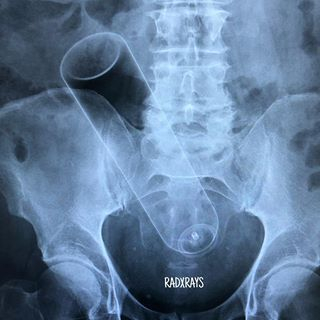

据统计,在急诊室中,男性“失物招领”的情况是女性的40倍,大部分失物是在肠道中被发现的,而且花样繁多……